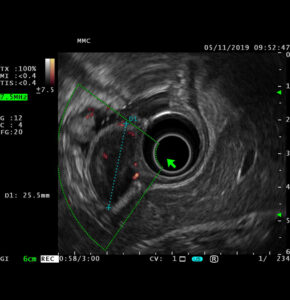

Эндоскопическая ультрасонография (ЭУС) – это высокоинформативный метод диагностики воспалительных и опухолевых заболеваний панкреато-билиарной зоны (поджелудочной железы, большого дуоденального сосочка, желчного пузыря и желчевыводящих путей) и желудочно-кишечного тракта (пищевода, желудка, двенадцатиперстной и толстой кишки), болезней печени и желчевыводящих путей, совмещающий возможности эндоскопического и ультразвукового исследований. Высокая разрешающая способность метода позволяет выявлять минимальные патологические изменения размерами до 1 мм, что превосходит возможности ультразвукового исследования (УЗИ), компьютерной томографии (КТ) и магнитно-резонансной томографии (МРТ).

ЭУС проводится при помощи специального прибора – ультразвукового эндоскопа, на дистальном конце которого расположен ультразвуковой датчик. В отличие от стандартных эндоскопических методов, ЭУС позволяет выявлять изменения не только внутренней видимой поверхности, но и всех слоев стенки органов желудочно-кишечного тракта и анатомических структур за ее пределами. Высокочастотные звуковые волны создают детальные изображения пищеварительного тракта и окружающих органов и тканей, включая поджелудочную железу, желчный пузырь, печень и лимфатические узлы.

Эндоскопическое ультразвуковое исследование работает аналогично УЗИ брюшной полости, за исключением того, что источник звуковых волн находится внутри тела. Когда высокочастотные звуковые волны распространяются от эхоэндоскопа, они попадают на ткани различной плотности и отражаются обратно. Например, эндоскопическое ультразвуковое исследование может выявить очертания опухоли или кисты, которые затем компьютер обрабатывает и отображает на экране в виде более светлых и темных участков.

Поскольку звуковым волнам не нужно проходить через кожу и мышцы, чтобы достичь внутренних органов, ЭУС обеспечивает лучший обзор желудочно-кишечного тракта и близлежащих органов, чем УЗИ брюшной полости.